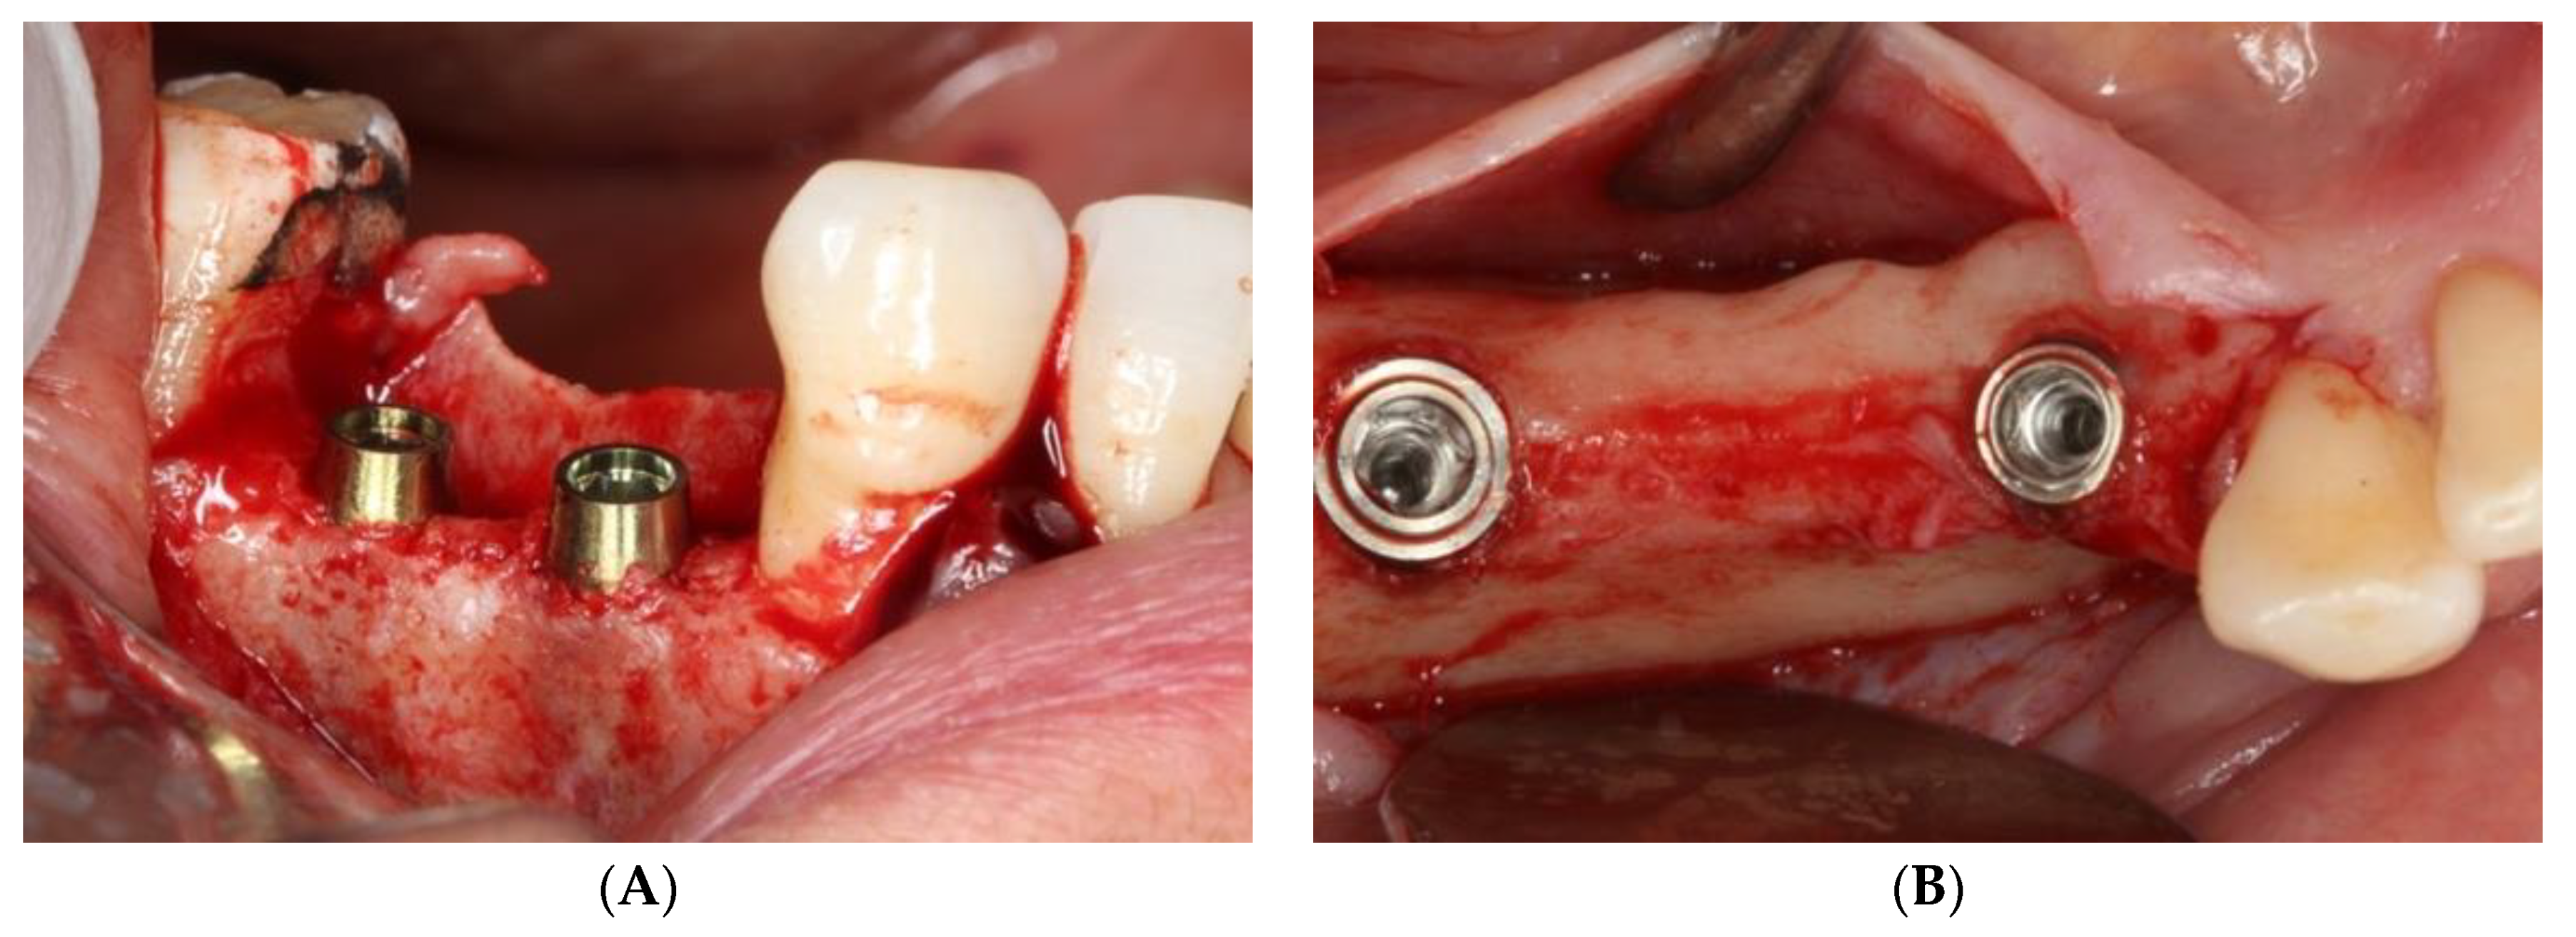

2. Material and Methods

2.3. Radiographic Technique and Bone Loss Measurement Method